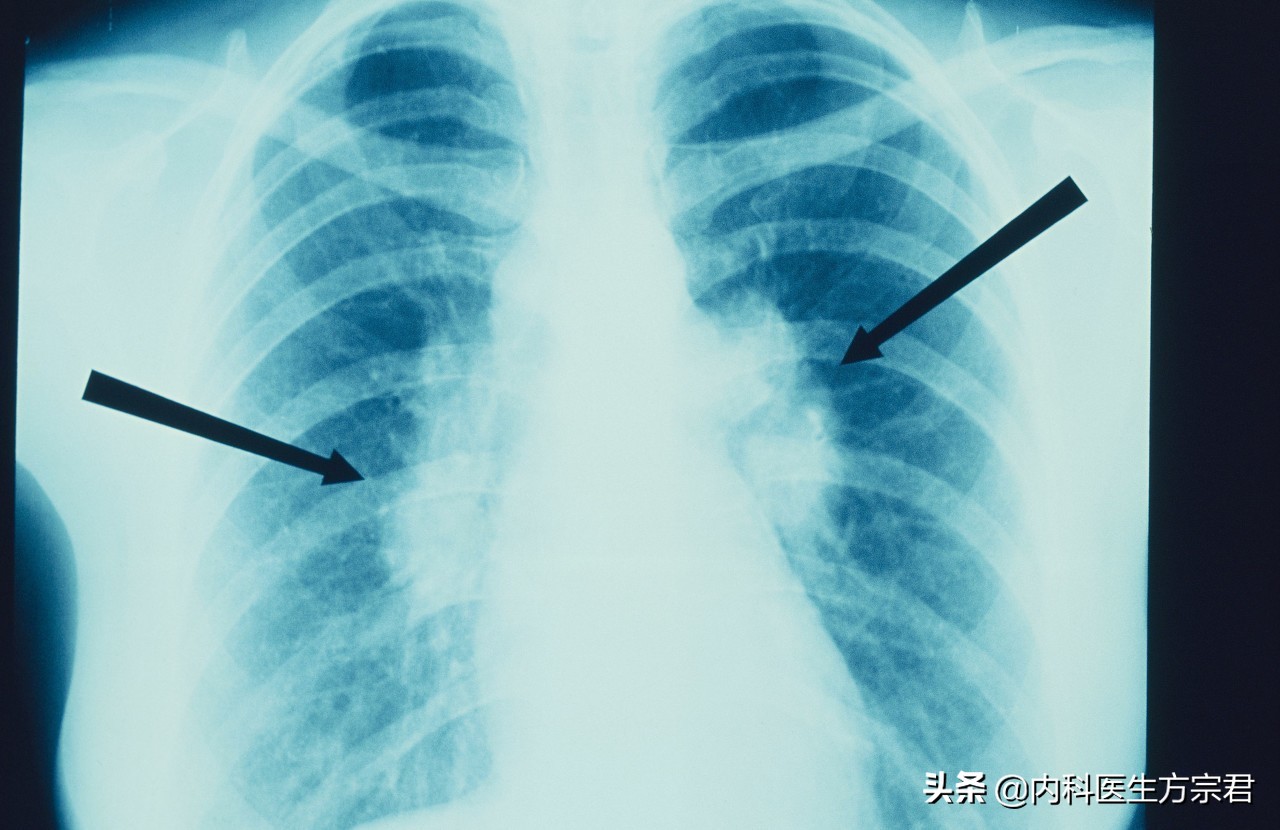

肺结节是一种影像的描述,通常指肺内直径小于三厘米的软组织病灶。根据其影像特点不同,分为实性结节和亚实性结节,其中亚实性结节又分为部分实性结节和磨玻璃样密度的结节,这些都是影像学的描述。

简单来说,肺结节医学上是指在肺实质内而不属于正常肺组织的结节状阴影,直径≤3厘米。可以是单独一个,也可以是多个。

肺结节根据直径大小,可分为:

肺内最大直径≤3厘米的病灶称为结节

肺内最大直径<1厘米的结节称为小结节

肺内最大直径<3毫米的结节称为微小结节

肺内最大直径>3厘米的不叫结节,称为肿块